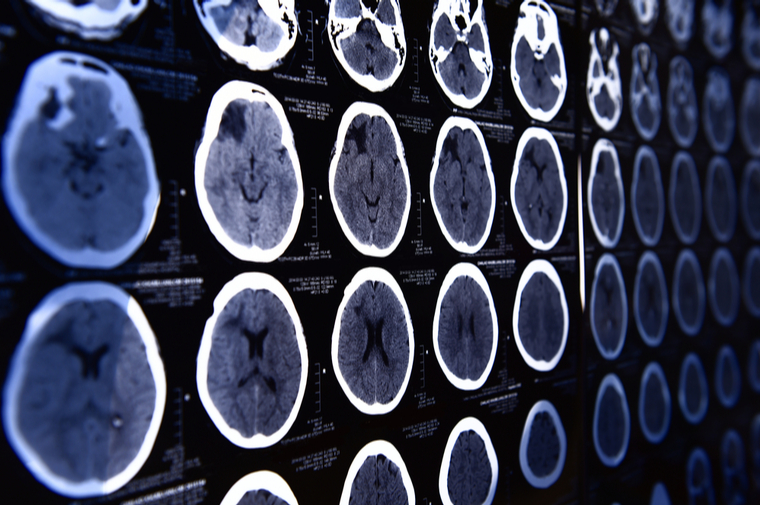

Two multidisciplinary groups headed by faculty from the McKelvey School of Engineering will be honing in on the brain, where currently, imaging techniques can penetrate about the depth of a couple of human hairs.

This is because tissue in the brain scatters and absorbs light, limiting the usefulness of microscopy. And other, non-optical imaging techniques (MRI, PET, and USI), only provide a narrow range of resolution.